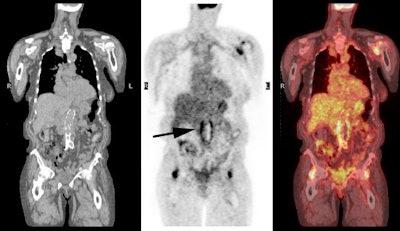

Vascular graft activity: The patient below had a prior graft repair of an ascending aortic aneurysm. Tracer uptake can be seen in the ascending aortic graft (black arrows). The patient also has a left upper lobe lung cancer (red arrows). |

|

Vascular graft activity: Another example of an asymptomatic patient with an aortic stent graft demonstrating tracer accumulation on FDG PET imaging. There is also inflammatory tracer uptake about the hips and left shoulder. |

|